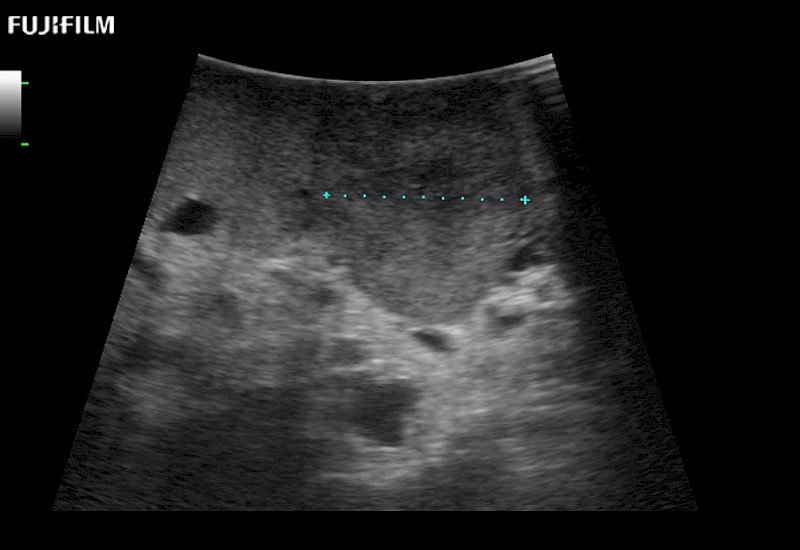

Curved array 4-way laparoscopic transducer for better visualization of targeted lesions.